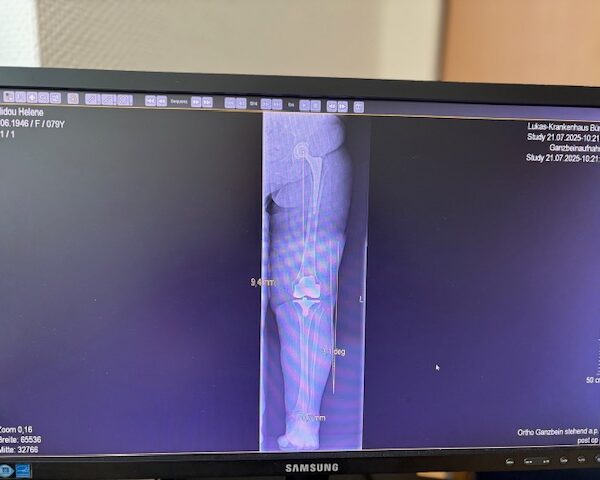

Ο προεγχειρητικός ψηφιακός σχεδιασμός

Πραγματοποιήθηκε σε ειδική ακτινογραφία ολόκληρων των δύο κάτω άκρων. Σε αυτό το ψηφιακό μοντέλο σχεδιάστηκε με ακρίβεια το είδος, το μέγεθος και η ακριβής θέση των προθέσεων, με βάση τα ανατομικά χαρακτηριστικά της ασθενούς.

Ο ψηφιακός σχεδιασμός επιτρέπει απόλυτη εφαρμογή των μοσχευμάτων, ελαχιστοποιώντας τα περιθώρια απόκλισης και εξασφαλίζοντας άριστη ευθυγράμμιση και κινηματική ισορροπία του γόνατος.